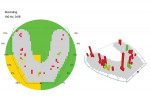

This was an astonishing and highly unexpected development, and the clinician proceeded to try to determine a cause for the problem in order to correct it. After several diagnostic tests were conducted, an OccluSense measurement was taken, which revealed that the patient's occlusion was completely unbalanced (Figure 11) and unprotected. While the OccluSense had not been used at the initial delivery appointment, the clinician did check the occlusion before dismissing the patient. However, because the patient had a complete mandibular denture, the occlusion that he demonstrated at his prosthesis delivery must have been different from the occlusion shown at this emergency appointment.